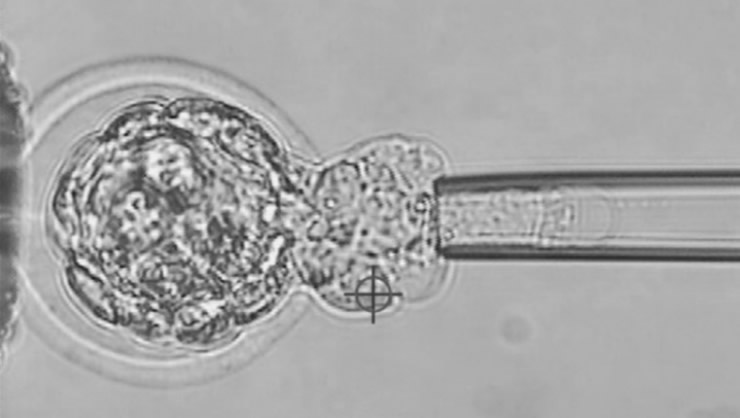

胚盤胞(5日目の胚)から実際に生検を行っている様子

染色体異常に関する着床前診断(PGT-A・PGT−SR)は現在日本産科婦人科学会主導のもと日本全国で行っている多施設共同研究の一環として、条件(反復ART不成功、反復流産、ご夫婦の染色体構造異常)を満たした患者さんに行っています。染色体異常のない受精卵から優先的に移植することで、妊娠に至るまでの移植回数が減ることが示唆されております。